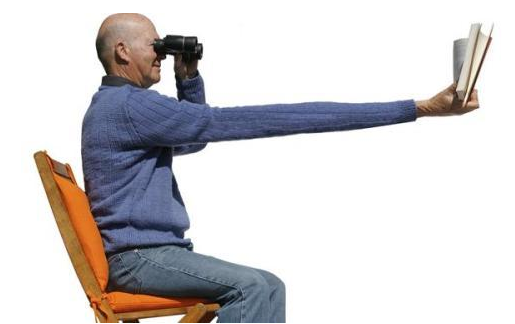

注意关节的锻炼并有效控制强直的发生

怎么来预防强直的复发有哪些是要注意

怎么来预防强直性脊柱炎的发生

强直的预防怎么控制发生

强直的预防方法看看有哪些

如何有效预防强直性脊柱炎?

成都强直医院医生:生活中强直性脊柱炎怎样预防?

怎样预防强直性脊柱炎的危害?需做好以下三点

成都强直专科医院,大家要认真对待强直性脊柱炎的预防工作

成都强直性脊柱炎医生,你了解强直性脊柱炎的具体预防环节吗